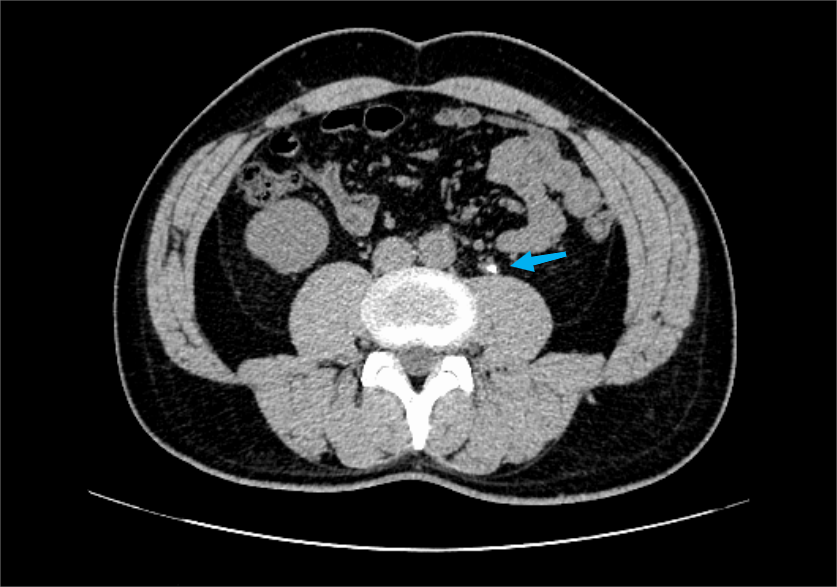

到了医院一做彩超,真相大白:左侧输尿管上段长了个 7 mm*5 mm 大小的结石,左肾还有轻度的积水。

其中,体外冲击波碎石术是利用体外产生的冲击波聚焦于体内的结石使之粉碎,继而将其排出体外达到治疗目的的治疗方法。

搞清楚情况的杨先生接受了手术,手术顺利完成。